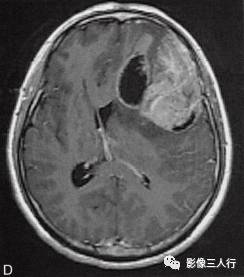

左侧额颞叶多形性胶质母细胞瘤

A.T1WI横断面;B.T2WI横断面;CFLAIR横断面;D.T1WI增强;E.T1WI增强冠状面;F.T1WI增强矢状面;G.HE×40;H.GFAR( )×40

影像学表现:

左侧额颞叶见较大不规则囊实性肿块,大小约5.4cm×8.3cm,平扫T1WI呈低信号、T2WI呈高信号(图A、B),肿块内有斑片状囊变区;增强扫描肿块实性部分呈不均匀明显强化,囊性部分呈环形强化(图D~F)。肿块占位效应明显,周围见环形水肿(图C)。